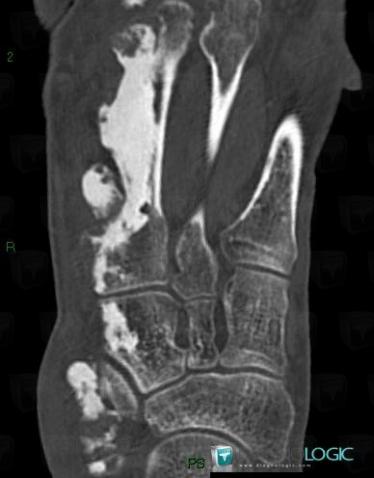

Die Diagnose wird im Röntgenbild gestellt. Es finden sich auf Dermatome begrenzte streifenartige sklerosierte Verdichtungen an Wachstropfen erinnernd, die von einer Kerze abfließen.